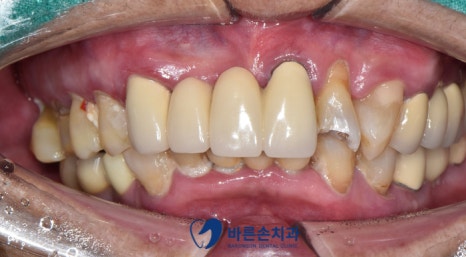

치아가 깨졌다며 내원해주신 환자분입니다.

구강 내 사진으로 다시 확인해보겠습니다.

엑스레이 사진에도 보였듯이 치아가 많이 깨져있는 상태입니다..

일단은 치아를 다듬어서 크라운만 해보자는 계획이었고

다듬는 중에 너무 신경과 가까우면 신경치료 가능성이 있다고 설명드렸습니다.

다행히도 신경이 드러나거나 하지 않아서!!

레진코어 후 크라운이 가능했습니다.

파절되어있던 치아를 다듬어 크라운으로 깔끔하게 씌웠어요ㅎㅎ

치아 색도 옆에 보철물과 맞춰 제작하여

더 보기 좋게 만들었답니다^^.